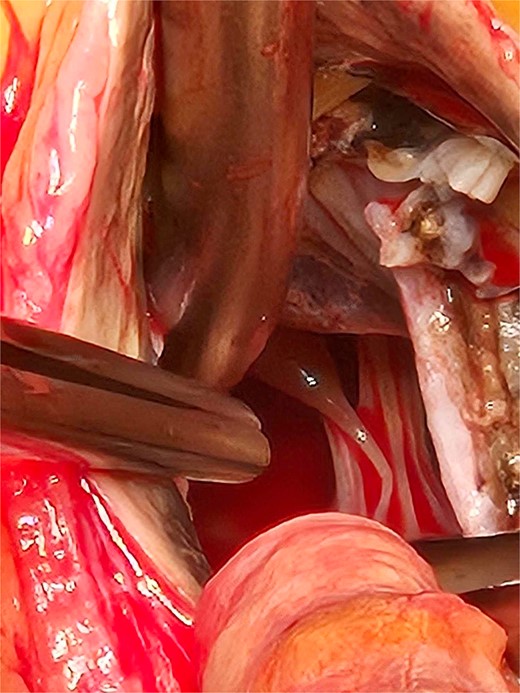

Based on these findings, the patient underwent surgical aortic biological valve replacement and coronary artery bypass grafting (CABG) using a left internal mammary artery graft to the LAD. Intraoperatively, unexpected ochronotic pigmentation was observed in the aortic and mitral valve leaflets, papillary muscles, and the intimal layer of the aortic root, presenting as patchy black discoloration (Figs 1–3). Subsequent biochemical analysis confirmed elevated homogentisic acid levels in the urine, consistent with alkaptonuria.

The patchy ochronotic discolouration can be visualized along the aortic root walls, and along the aortic valve leaflets, being more prominent along areas of heavy calcification.